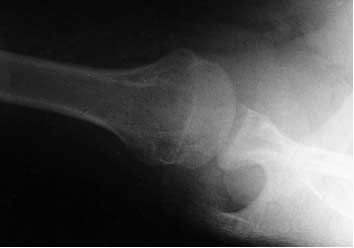

<Westpoint view>

촬영목적 : 어깨의 불안정성을 가진 환자의 접시오목테두리(glenoid cavity rim)의 뼈이상 등 병변의 유무 관찰.

촬영point : 위팔뼈머리는 부리돌기와 겹침이 없고 위팔뼈머리와 접시오목 사이의 관절이 선명하게 나타나야함.

- West point view : Bankart 병변 잘 볼 수 있음.

방카트 병변(Bankart lesion) : 전방 관절와 순-인대 복합체의 파열.

힐삭스 병변(Hill-Sachs lesion) : 상완골두 부분에 골 결손이 생긴 것.